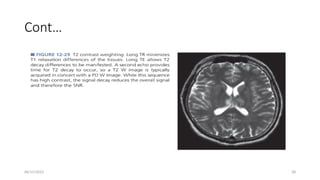

T2 Weighting(T2W)

• T2 contrast weighting follows directly from the PD-weighting sequence

• reduce T1 differences in tissues with a long TR, and emphasize T2 differences

with a long TE.

• The T2-weighted signal is generated from the second echo produced by a second

180-degree pulse of a long TR spin echo pulse sequence,

• where the first echo is proton density weighted, with short TE.

cont…

• T2 contrast differences are manifested by allowing M xy signal decay .

• Compared with a T1-weighted image, CSF is bright, and gray and white matter

are reversed in intensity.

• As TE is increased, more T2-weighted contrast is achieved.

• but at the expense of less M xy signal and greater image noise.